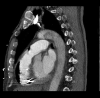

Venous air embolism (VAE) occurs when air is introduced into the venous system and subsequently travels into the right heart and pulmonary circulation. VAE mainly occurs from air that is forced by positive pressure or drawn in by negative pressure. We present a rare case of fatal VAE that occurred during a routine dental root canal procedure. A 69-year-old male was undergoing a root canal procedure at an outpatient dental office under local anesthesia. During the procedure, he went into cardiopulmonary arrest. He was resuscitated, and return of spontaneous circulation was achieved. Thoracic computed tomography was performed and revealed large amounts of air within the right ventricle and portal venous system. VAE should be recognized as a potentially fatal complication resulting from routine dental procedures.